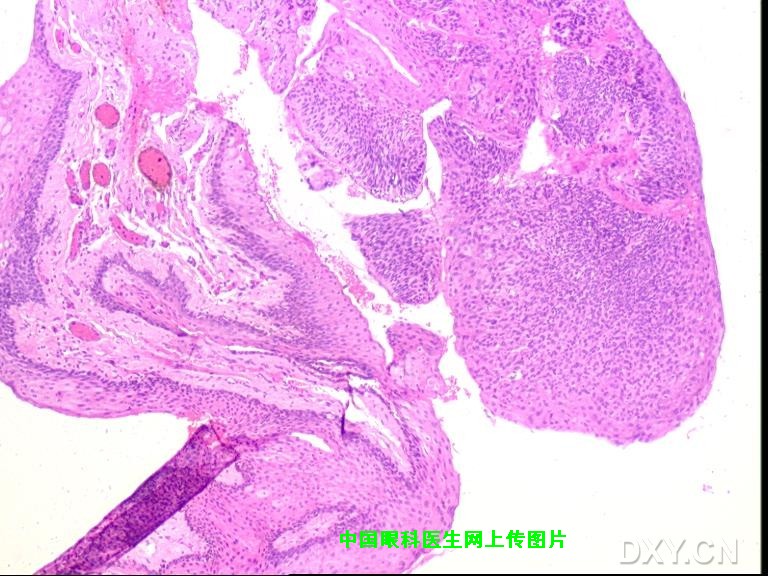

Posted by: gl6365 Posted on: 2008-03-10 20:55

以下为病人术后2周照片。 病理报告:鳞状上皮乳头样增生伴轻度不典型增生。

qizhieye wrote: 这是我以前的患者图

非常感谢您所提供的图片,从形态上看,的确与我所报道的病例极为相像,随之而来的是诊断上的困惑,我们诊断为Bowen病(角膜上皮内上皮癌)的主要依据如下: 1.睑裂区角膜缘病变,灰白色半透明隆起,发展缓慢且症状轻微; 2.手术当中非常容易剥离,说明病变没有突破基底膜; 3.当然最有发言权的应该是病理所见(金标准);我曾将病理图片发到丁香园病理讨论区,但回应者不多,看来还是得请咱们眼科特别是病理方面的同行来给大家解释一下该病例的病理图片。 另外如果可能也请您将您所报道病例的术后情况以及病理所见提供给大家。

(缩略图,点击图片链接看原图) |

感谢提供的文献,看来我们的病理取材后的处理手法有待提高,切除的组织发生了卷曲。 |